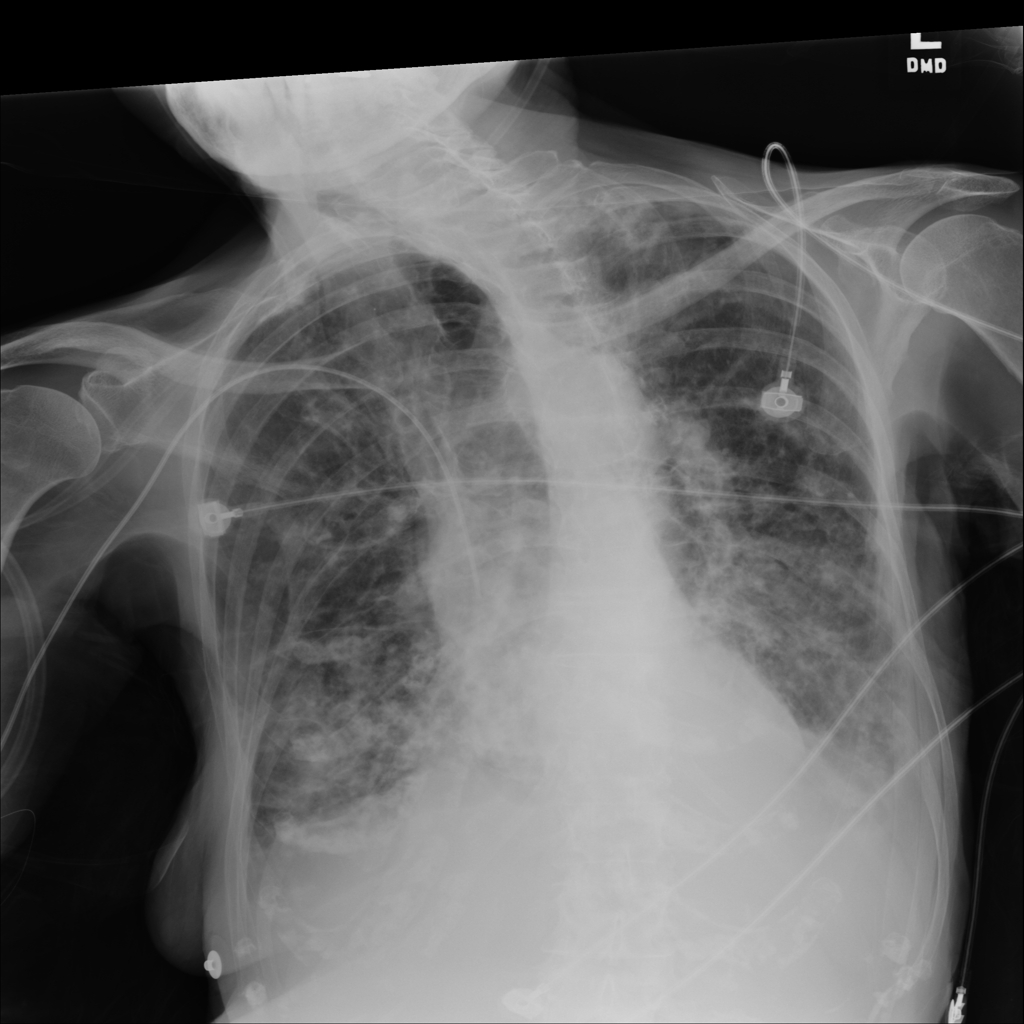

PAT-C1A7 · IMG-055Consolidation

PAT-C1A7 · IMG-055

AP